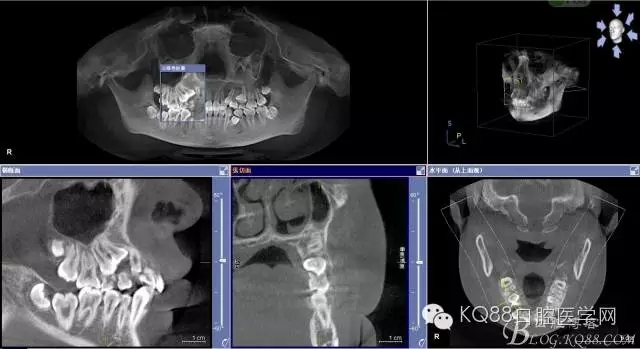

患者、女、15歲,主訴:右側(cè)前磨牙未萌出,要求口腔檢查。正畸科經(jīng)過臨床檢查,建議拔除14、24、34、44、54、55、65、74,然后做正畸治療。cbct檢查:14高位埋伏于15、13之間,拔除難度較大,遂術(shù)前與患者家長溝通,講明拔除14可能存在的臨床風(fēng)險(xiǎn),患者同意手術(shù)方案,簽知情同意書。

圖2.術(shù)前cbct檢查:54、55乳牙滯留,14、15埋伏阻生,14位于15的上方。

圖4.從局部影像,可以看出14牙冠位于15牙冠與13牙根之間。

圖5.水平剖面觀:14牙冠緊鄰15與13牙根之間,要求分牙一定要小心謹(jǐn)慎